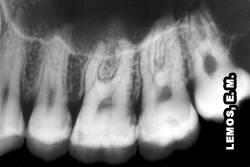

Aspectos radiográficos de alguns tratamentos endodônticos variando o número de canais e a configuração das raízes mésio-vestibulares |

| Raiz mésio-vestibular - 1 canal | Raiz mésio-vestibular - 2 canais independentes | Raiz mésio-vestibular - 2 canais independentes no terço cervical unindo-se no terço apical | ||

![]() |